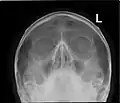

Paranasal sinuses

Lateral projection of the paranasal sinuses